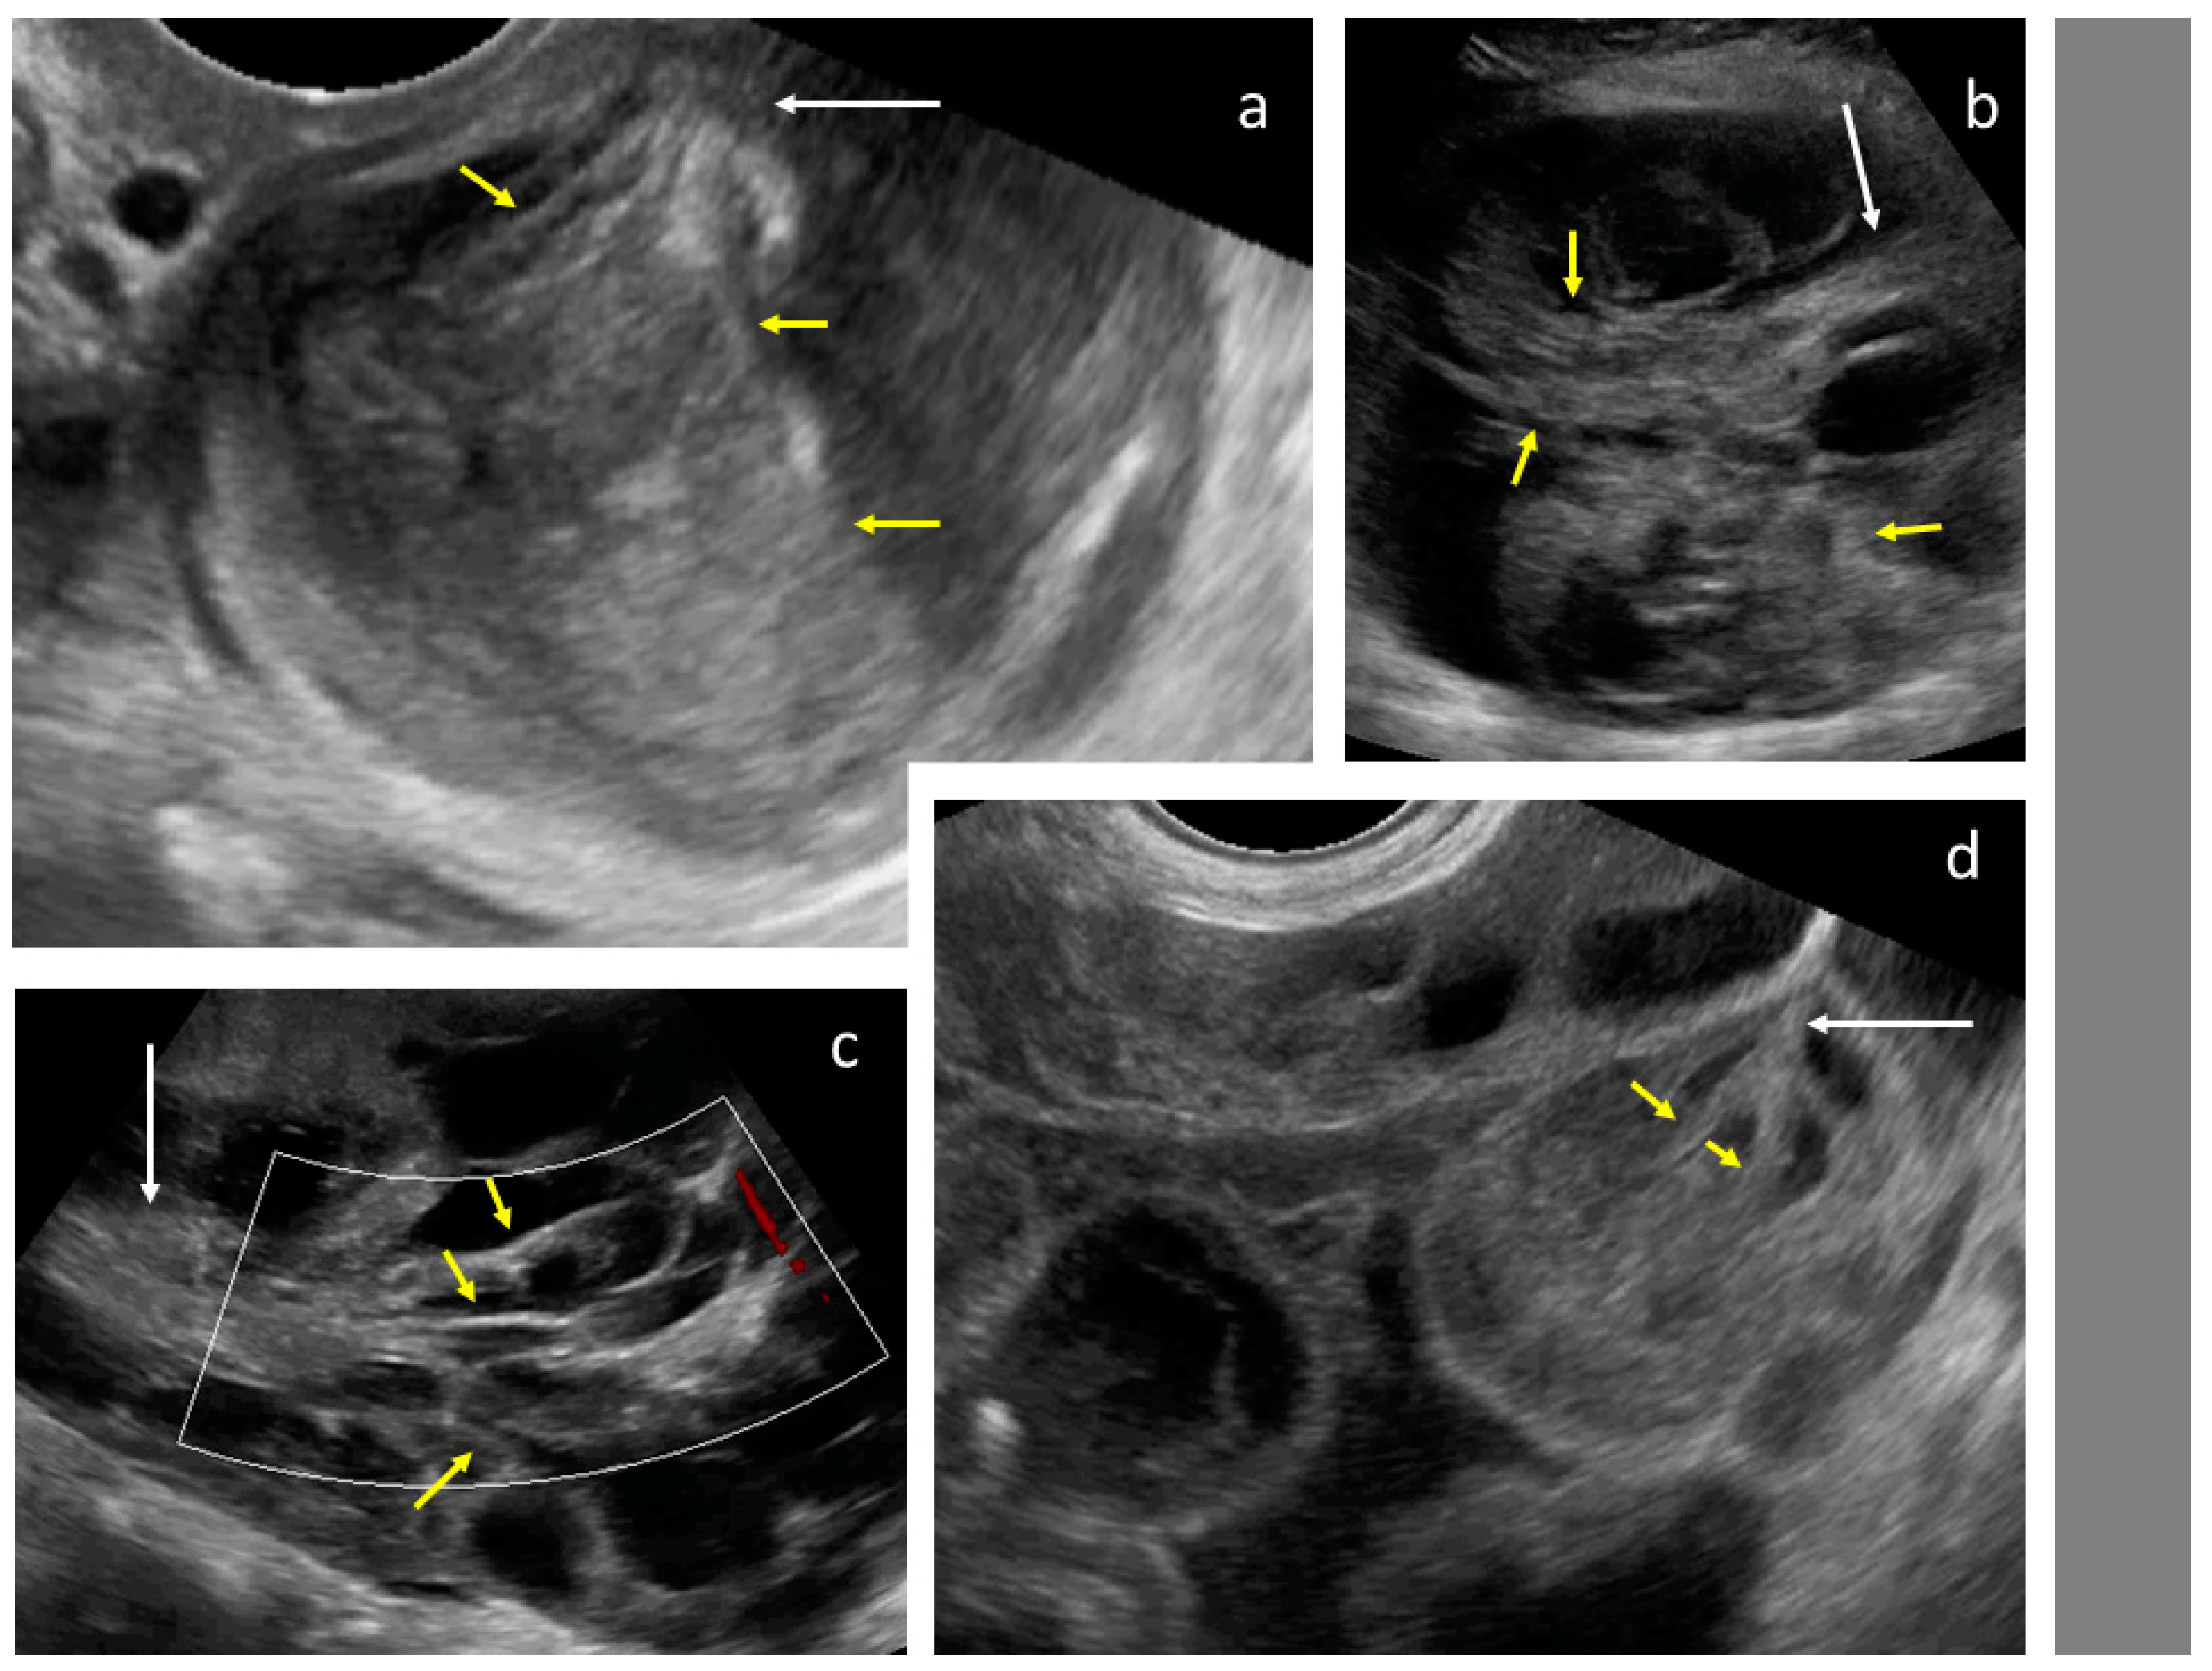

After the collection of cases for the study was closed, a new observation was noted (by M.S.) when analyzing the videoclips of ovarian mCRC in detail. A tree-like sign was detected in multilocular-solid tumors, with parallel, closely-localized, septa (“trunk”) later branching in different directions (“branches”), forming an image resembling a tree (Figure 5, Video S3). Interestingly, the tree-like sign was not detected in any of matched controls with primary OC.

Figure 5.

Tree-like sign in a multilocular-solid tumor. White arrows indicate the “tree trunk”; yellow arrows indicate “tree branches”.

Ovarian mCRC tumors were significantly larger, a necrosis sign was more often present, and tumors had an irregular wall or were fixed less frequently; ascites, omental cake, and carcinomatosis were less common in mCRC than primary OC (Table 1). In a subgroup of patients with ovarian mCRC who had not undergone treatment for CRC in anamnesis, tumors were larger and had fewer papillations and more locules compared with primary OC; these patients also had abdominal metastases detected with an ultrasound less often than patients with primary OC (Figure 6).

In this study, previous treatment for CRC was the strongest clinical variable; if this is present, and there is an ovarian tumor, metastasis should be suspected, regardless of ultrasound parameters. All but one patient who had previously had CRC underwent chemotherapy, and hence had high-risk disease at diagnosis. On the ultrasounds, ovarian mCRC was mostly solid or multilocular-solid. Compared with primary OC, mCRC tumors more often had signs of necrosis in the solid components; less often, they had irregular internal walls, if locular, and were more mobile. Those with ovarian mCRC who had not previously undergone treatment for CRC had larger tumors with fewer papillations and more locules compared with primary OC tumors. Upon abdominal scanning for cancer dissemination, patients with OC had ascites, peritoneal carcinomatosis, and omental involvement more often, and liver metastases less often than those with mCRC. In addition to the previously described layered structure of a multilocular metastatic tumor [7], an ultrasound image resembling a tree was noted. Primary OC and mCRC are graphically compared in Figure 9. The most accurate methods for discriminating ovarian mCRC from primary OC were the proposed decision tree model and SA, which both generated fair AUC values. Application of the ADNEX model in this patient population resulted in a poor AUC value when CA-125 was included, and failed without CA-125. Moreover, the absolute percentage and RR values for risk of metastases were higher than those at risk of primary OC; however, it is not clear whether these differences are clinically significant.